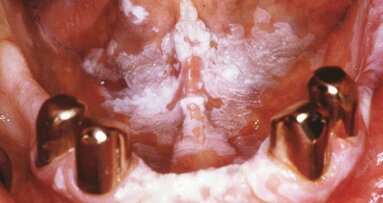

KÖLN – Das Zahnfleisch ist entzündet. Die Parodontitis ist so stark, das Zähne verloren gehen könnten. Aber der Patient versichert glaubhaft, Mund und Zähne regelmäßig und gründlich zu reinigen. Dann bringt ein Hinweis im Beratungsgespräch den Stein ins Rollen. Der Patient wird seit einiger Zeit mit dem Verdacht auf Osteoporose behandelt. Da der Zahnarzt kürzlich einen Fachartikel gelesen hat, kommt ihm ein anderer Verdacht. Möglicherweise handelt es sich in diesem Fall um Hypophosphatasie.

Ein Glücksfall für den Patienten, denn bevor ein Arzt eine Hypophosphatasie, kurz HPP, diagnostiziert, ist der Patient häufig anders behandelt worden. Seltene Erkrankungen sind auch für erfahrene Ärzte schwer zu erkennen. Das liegt an den Symptomen, die - in diesem fiktiven Beispiel - auf Rachitis, Gicht, rheumatischen Erkrankungen oder Osteoporose deuten.

Weltweit sind nur 6.000 bis 8.000 seltene Erkrankungen bekannt. In Deutschland schätzen Experten, dass rund vier Millionen Menschen an einer seltenen Erkrankung leiden. Bei ca. 15 Prozent aller seltenen Erkrankungen zeigen sich Hinweise der Erkrankung im Zahn-, Mund-, Kiefer- und Gesichtsbereich.